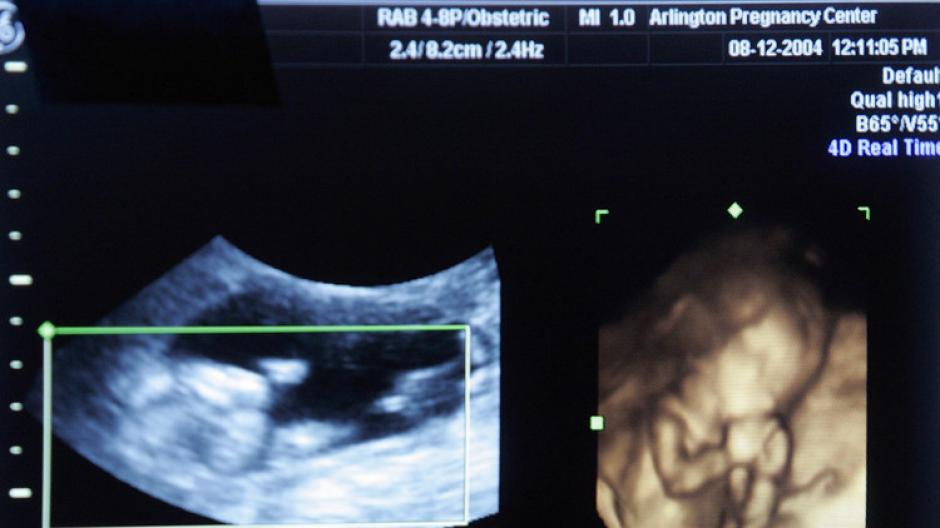

Una ecografía con la máscara de Scream se viraliza.